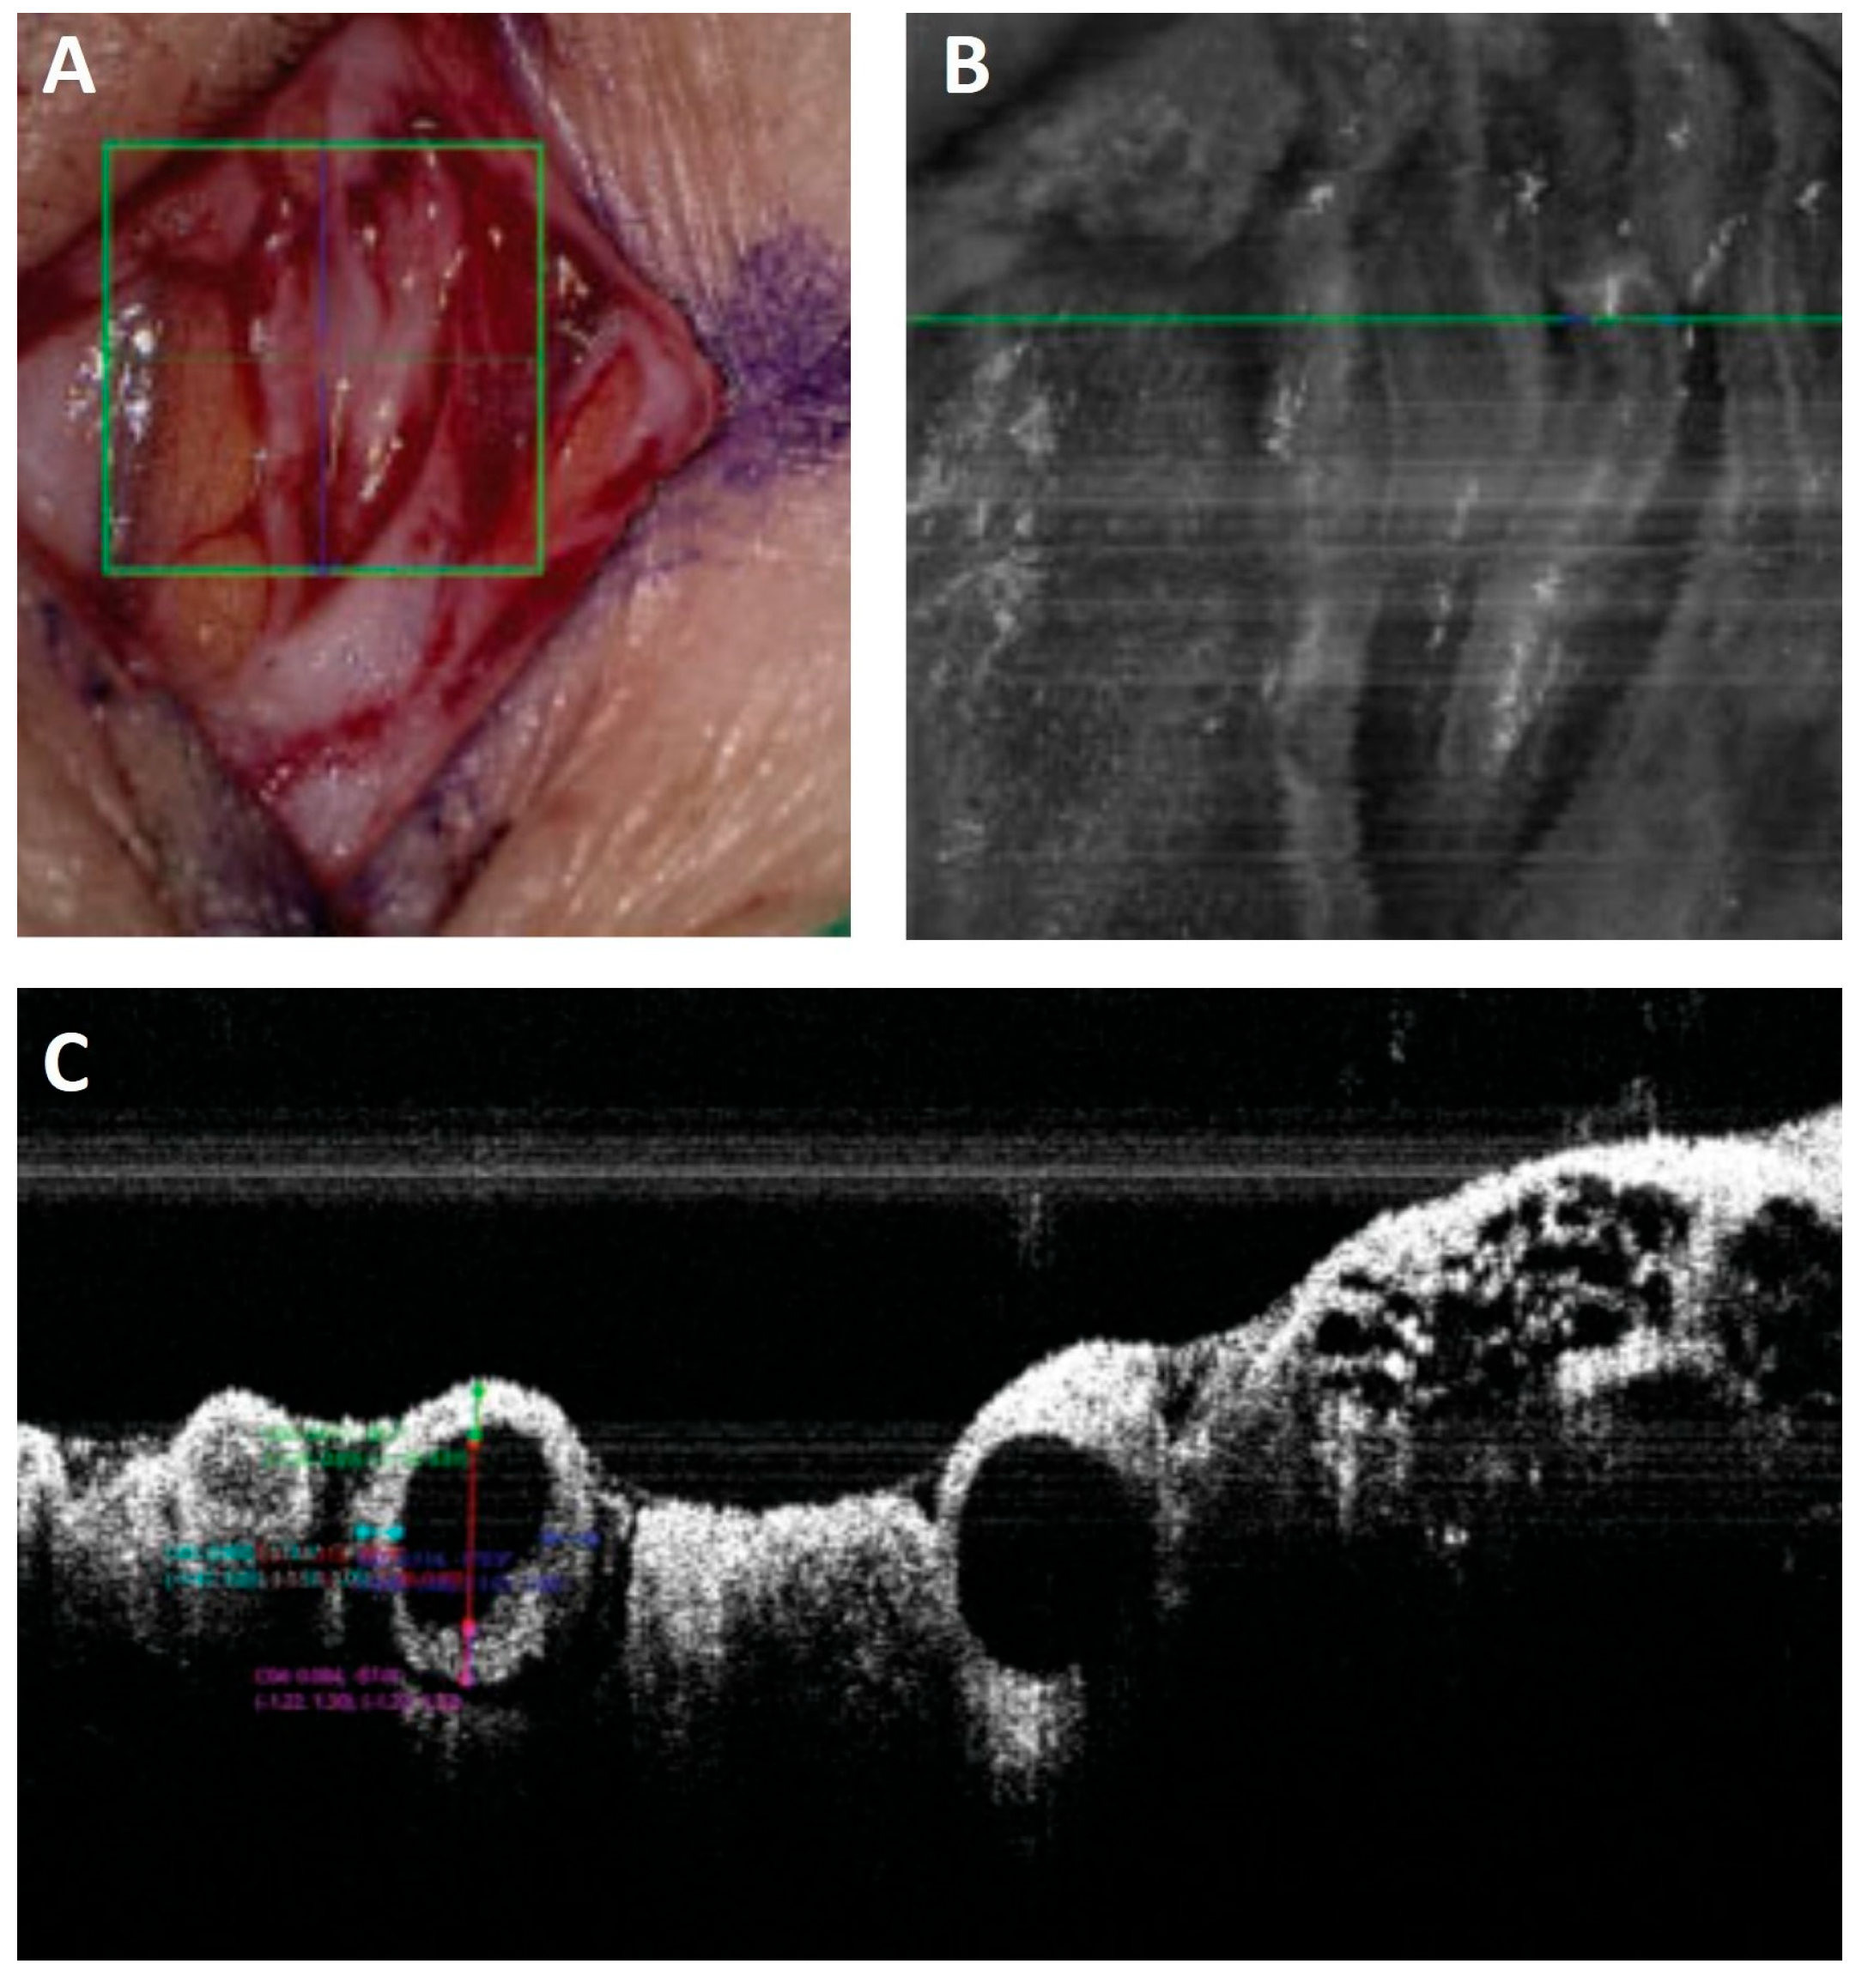

- Hayashi, A.; Yoshimatsu, H.; Visconti, G.; Sujarittanakarn, S.; Giacalone, G.; Hayashi, N.; Yamamoto, T.; Yang, J.C.S.; Hong, J.P. Intraoperative Real-Time Visualization of the Lymphatic Vessels Using Microscope-Integrated Laser Tomography. J. Reconstr. Microsurg. 2021, 37, 427–435. [Google Scholar] [CrossRef] [PubMed]

- Yang, J.C.S.; Wu, S.C.; Chiang, M.H.; Lin, W.C.; Hsieh, C.H. Intraoperative Identification and Definition of “Functional” Lymphatic Collecting Vessels for Supermicrosurgical Lymphatico-Venous Anastomosis in Treating Lymphedema Patients. J. Surg. Oncol. 2018, 117, 994–1000. [Google Scholar] [CrossRef]